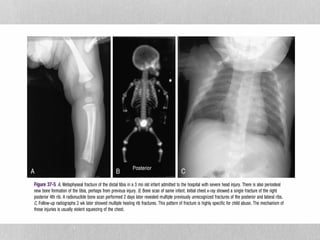

FRACTURES

hild has one or more fractures

in the absence of a medical

condition that predisposes to

fragile bones (for example,

osteogenesis imperfecta,

osteopenia of prematurity) or

if the explanation is absent or

unsuitable

• Presentations include:

• fractures of different ages

• X-ray evidence of occult fractures

(fractures identified on X-rays that

were not clinically evident). For

example, rib fractures in infants.

FRACTURES hild has oneor more fractures in the absence of a medical condition that predisposes to fragile bones (for example, osteogenesis imperfecta, osteopenia of prematurity) or if the explanation is absent or unsuitable • Presentations include: • fractures of different ages • X-ray evidence of occult fractures (fractures identified on X-rays that were not clinically evident). For example, rib fractures in infants.